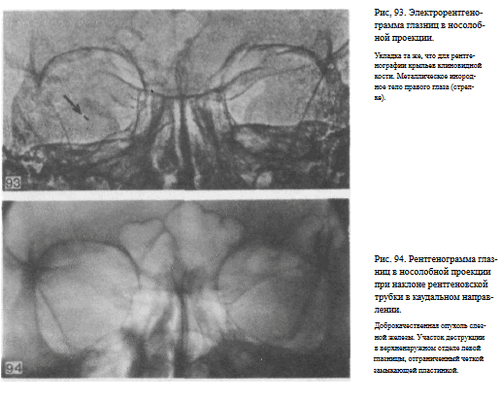

В качестве примера информативности снимка глазниц в носолобной проекции для выявления инородных тел глаза и деструктивных изменений стенок приводим два наблюдения.

Одно из них — случай ранения глаза металлической стружкой (рис. 93), другое — случай деструкции верхненаружного края глазницы при доброкачественной опухоли слезной железы (рис. 94).

Информативность снимка. На снимке хорошо видны вход в глазницу, структура ее стенок, иногда малое и большое крыло клиновидной кости (рис. 89). На снимке в этой проекции могут быть выявлены деструктивные изменения стенок глазницы и инородные тела в ее полости (рис. 90, 91). Для выявления изменений в области верхней стенки глазницы (например, при

диагностике переломов) снимок целесообразно выполнять не в носоподбородочной, а в подбородочной проекции.